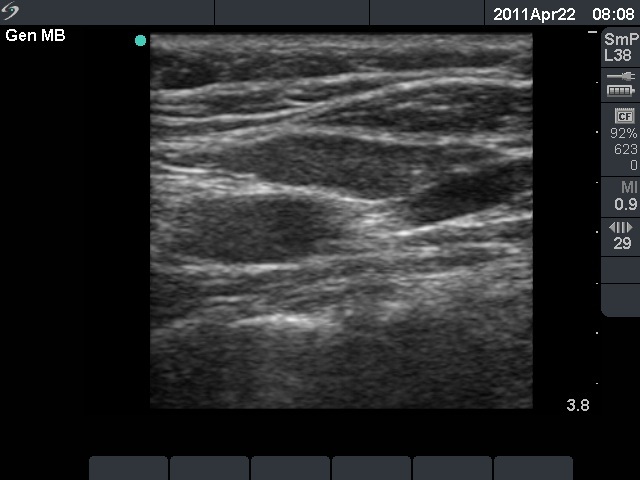

Ultrasonography revealed three hypoechogenic lesions in the left thyroid bed. Two of them were vessels while the third one resembled a lymph node or a thyroid lesion on transverse view. Longitudinal scan disclosed that the lesion in question was in fact a muscle fiber.

Comment. It is very important to perform a thyroid ultrasound examination in two different sections.